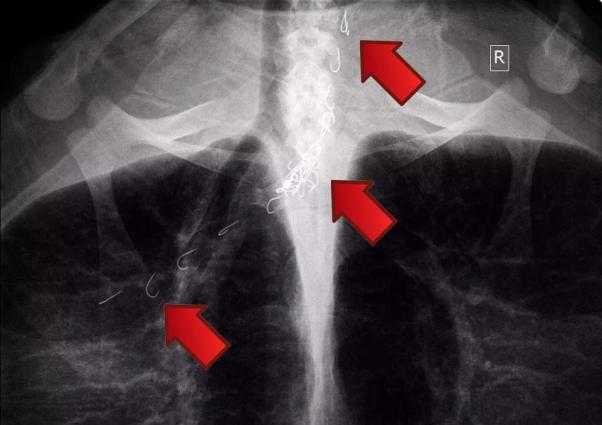

Η ακτινογραφία έδειξε τι είχε καταπιεί και πόσο βαθιά είχαν φτάσει τα αγκίστρια. Το Σάββατο 11 Οκτωβρίου οι ειδικοί άνοιξαν μια τομή στο λαιμό της καρέτα και έβγαλαν την πετονιά και τα 26 αγκίστρια. Τρία από αυτά όμως εξαιτίας του σημείου που έχουν αγκιστρωθεί έχουν μείνει στο σώμα του ζώου.

Στη χελώνα χορηγήθηκαν ειδικά λάδια που θα βοηθήσουν ώστε τα τρία εναπομείναντα αγκίστρια να ξεκολλήσουν και να απορριφθούν από το σώμα της εξήγησε στο www.zoosos.gr ο Γιάννης Ορφανός που ήταν ένας εξ αυτών οι οποίοι την εντόπισαν να κολυμπάει τυλιγμένη με τις πετονιές. Η καρέττα τώρα αναρρώνει στη μικρή πισίνα και θα μεταφερθεί στη μεγαλύτερη μόλις τις αφαιρέσουν τα ράμματα. Σε μερικούς μήνες θα κολυμπάει και πάλι ελεύθερη στην Αγία Άννα της Νάξου.